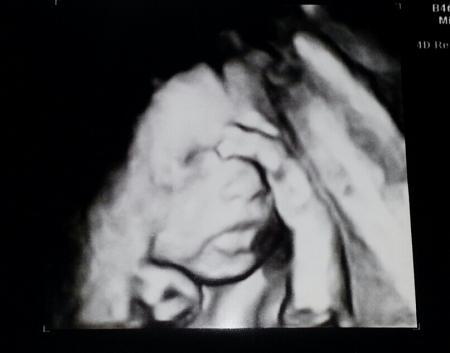

hallo ihr lieben, bin etwas im stress und antworte darum gerade gar nicht so fleißig wie ich gern würde :o( will aber wenigstens noch schnell von gestern berichten. biggi entwickelt sich weiter prächtig, bei 23+0 hat sie uns mit ca 512g und 28cm beglückt. brav zeitgerecht. gebärmutterhals ist auch noch phantastisch lang. zur zeit ist sie auch wahnsinnig aktiv, das ist toll. selbst unser zweijähriger hat sie schon gespürt :o) habe wieder vermehrt linksseitige rückenschmerzen gehabt. hatte wie in der ersten ss auch die nieren im verdacht, aber da ist noch alles gut. scheint also "richtig rücken" zu sein. ischias ist es auf jeden fall nicht. naja da meine tape-fee da war hat sie gleich alles hübsch gemacht. am 4.1. fliegen wir nach teneriffa. heute feiern wir papierhochzeit wenn wir von teneriffa wieder kommen habe ich gleich am nächsten tag blutzuckertest und mein erstes ctg.

Ohhh wie süß das bild :-) die kleine brigitte ;-) hat soooo schöne lippen ... Freut mich das alles perfekt passt und es der kleinen maus gut geht! Wünsche euch einen scönen urlaub und ein frohes fest :-)

Schleiche mich mal ein :) Ein ganz tolles Foto!!! Freut mich, dass alles so super ist :) Liebste Grüße.

Freu mich so für dich, meine liebe Patin, dass alles gut ist (abgesehen vom Rücken, Sodbrennen & Co.). Aber das ist halt bei uns Alten so, gell. ;-)) Das Bild ist so schön. Ich hoffe, ich komme in dieser Schwangerschaft auch noch zu einem 3D Bild. Versuche mal, beim nächsten Termin meinen FA zu bestechen. :-) LG

Eure Bigi ist echt ne süsse! Schön dass alles so gut aussieht und die Maus sich so wunderbar entwickelt!

Was für ein süßes Bild! Schön, dass alles gut und schick entwickelt ist. Dann kann das Weihnachtsfest ja kommen. Alles Gute für Deinen Rücken! Die spanische Wärme tut bestimmt gut.